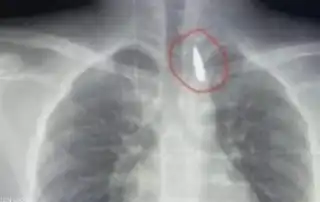

في جراحة نادرة ومعقدة.. أطباء مصريون بمشفى جامعة الإسكندرية يتمكنون ...